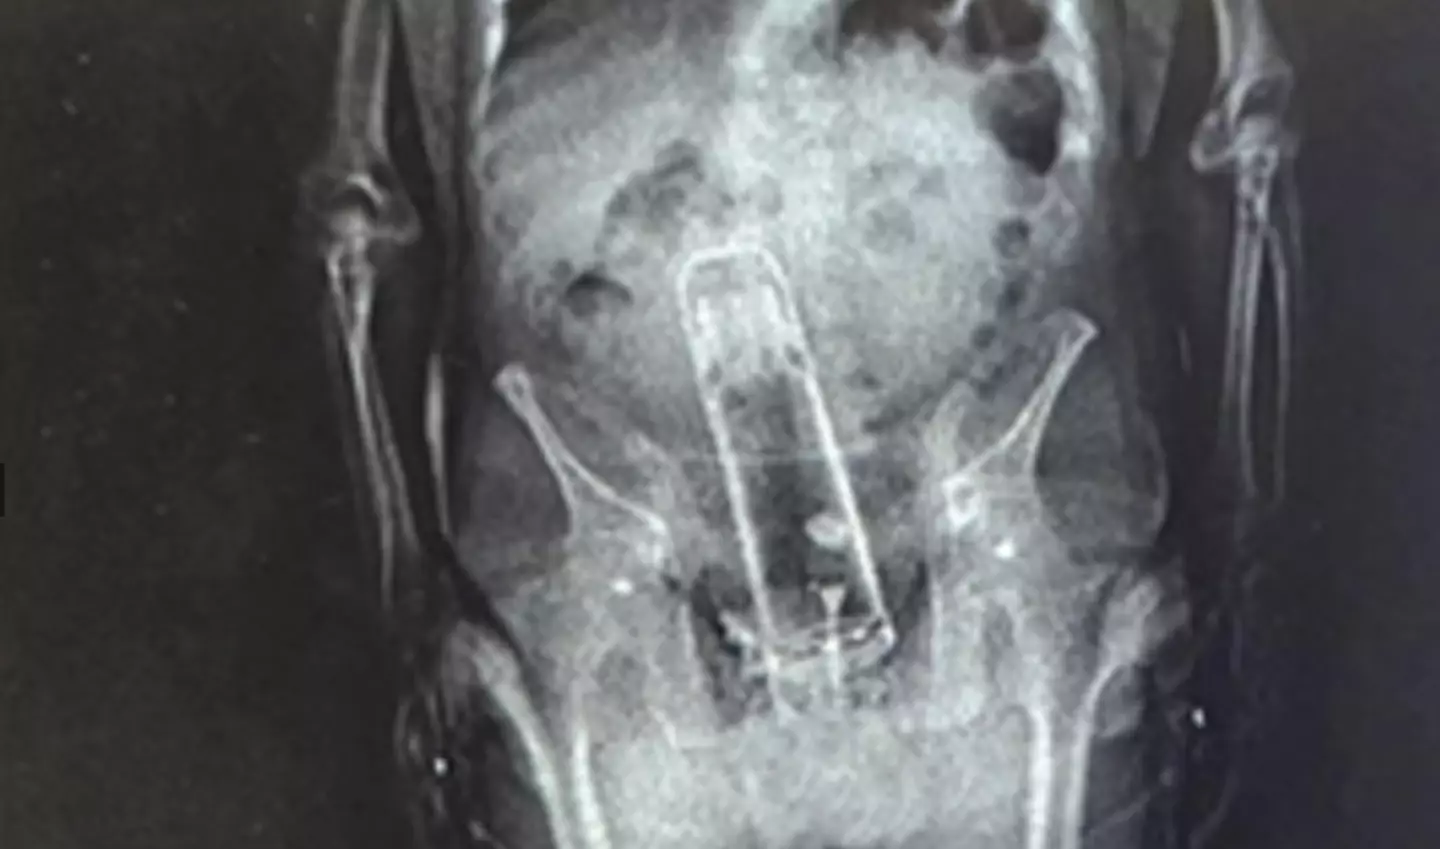

An X-ray conducted at the hospital showed a foreign object extending from his hip to his rib.

Discussing the thermos discovery, the sheriff explained: “You might have thought that Walter was bringing drugs into the jail. He brought a thermos into the jail. That’s right.

“He put it up the exit ramp. You know what I mean?”

Judd continued: “We said ‘Dude! What are you doing here?’ Well, I put that inside my body.’ He didn’t swallow it twenty-four hours earlier.”

As expected, Frymire was transported to a nearby hospital to have the thermos extracted.

Fortunately, medical professionals were successful in removing the object.